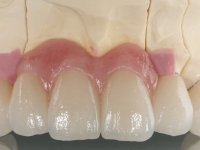

In view of the clinical situation, oral rehabilitation was proposed to improve the aesthetic appearance, but also to solve the lack of posterior teeth, seeking a functional and aesthetic rehabilitation. The plan included replacing the metal-ceramic bridge by a bridge with Zr infrastructure coated with coronary and gingival ceramics. The edentulous area of the first quadrant would be rehabilitated with 2 implants and a bridge of two elements. It was intended with this treatment plan, to recover the vertical dimension of the occlusion and to reshape the dental anatomy, thus creating a more natural aesthetic appearance.

Alginate impressions were made at both arches arcades, accompanied by intermaxillary registration relations and collecting information with facial bow facial bow. In the laboratory, a provisional bridge with 13 elements in autopolymerizable acrylic was built, in which a metallic reinforcement was included. Teeth 1.7 / 1.4 / 1.3 / 2.2 / 2.3 / 2.4 and 2.6 were used as pillars. The metal-ceramic bridge was removed after performing longitudinal cuts with diamond burs. The dental abutments were reprepared and the temporary bridge was relined in the mouth with self-curing acrylic. After confection of the provisional bridge, a gingival epithesis was made using composite resin with gingival tonality in order to function as a mock-up, which allowed the patient to preview the possibility of using gingiva shade ceramics in the final work. This option was approved by the patient. Subsequently, the placement of two implants in the first quadrant was planned and executed. The provisional monoblock was removed for placement of the implants, and after surgery was again cemented provisionally. After the osseointegration period, the impressions were made to the maxilla. In the anterior zone, impregnated gingival retraction cords were used, and in the posterior areas, kaolin paste was used. Implant printing utilized the open tray technique. The printing material used was soft and regular putty addition silicone, both fast-setting. In the laboratory, the model of provisional restorations and the gingiva epithesis mock-up served as orientation for waxing the infrastructure. The plaster work model and the waxing of the infrastructure were placed in a laboratory scanner and yielded a digital work model, in which the scanning of the waxed infrastructure was superimposed. This overlay facilitated the CAD design of the Zr infrastructure. Subsequently, the CAD drawing for a CAM milling process provided the Zr pieces. The infrastructure was pigmented with a pinkish coloration, which favors the subsequent placement of gum shade ceramic. During the modeling of the infrastructure, the need to increase the occlusal wear on tooth 1.4 was detected. This was done in the real working model cast and an acrylic wear control guide was created, which accompanied the proof of the infrastructures. Corrective wear and Zr parts test were performed in mouth. During the test, the color choice of the gum shade ceramic was reassessed. The treatment was finished in the laboratory, and after approval by the patient, was definitively placed in the mouth.